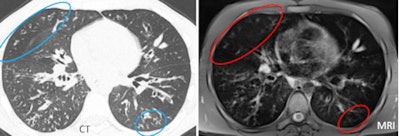

| MRI tended to underestimate the severity of disease at the lung periphery. |

"We found the same problem" as the earlier study, Ciet told AuntMinnie.com. "We saw disappearing anatomical structures like bronchiectasis, bullae [thin wall], and small plugs of mucus. Moreover it's quite difficult to differentiate between small mucus plugs and vessels at the periphery of the lung."